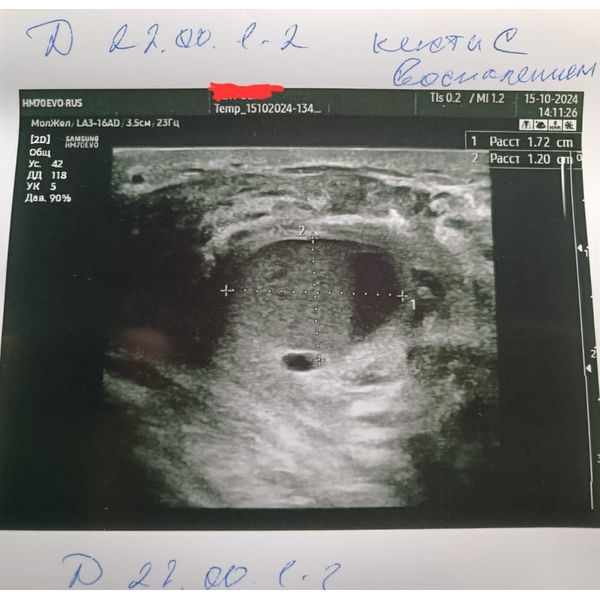

УЗИ молочной железы выявило:

- диффузный фиброаденоматоз (ФАМ) железисто-кистозного типа;

- простые кисты обеих молочных желёз от 5 до 10 мм;

- крупная киста в правой груди размером 17 × 12 × 20,6 мм с густым содержимым внутри;

- отёк и усиленный кровоток в тканях, окружающих кисту;

- увеличенный лимфоузел в правой подмышечной области с усилением кровотока, размер — 22 × 10 × 18 мм.